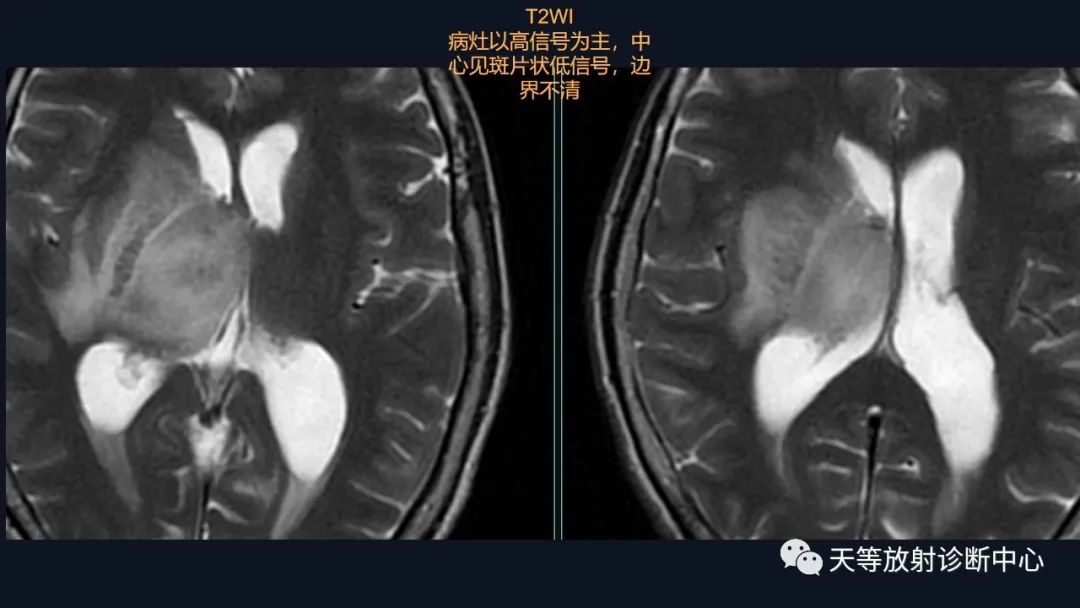

本病例影像学特点:

脑内占位的特点:

1、刀切征

2、凹陷征或肚脐凹征

3、尖角征

4、多发

5、DWI呈稍高信号

6、形态上怪异

6、NAA及Cho减低,出现导致LL峰。